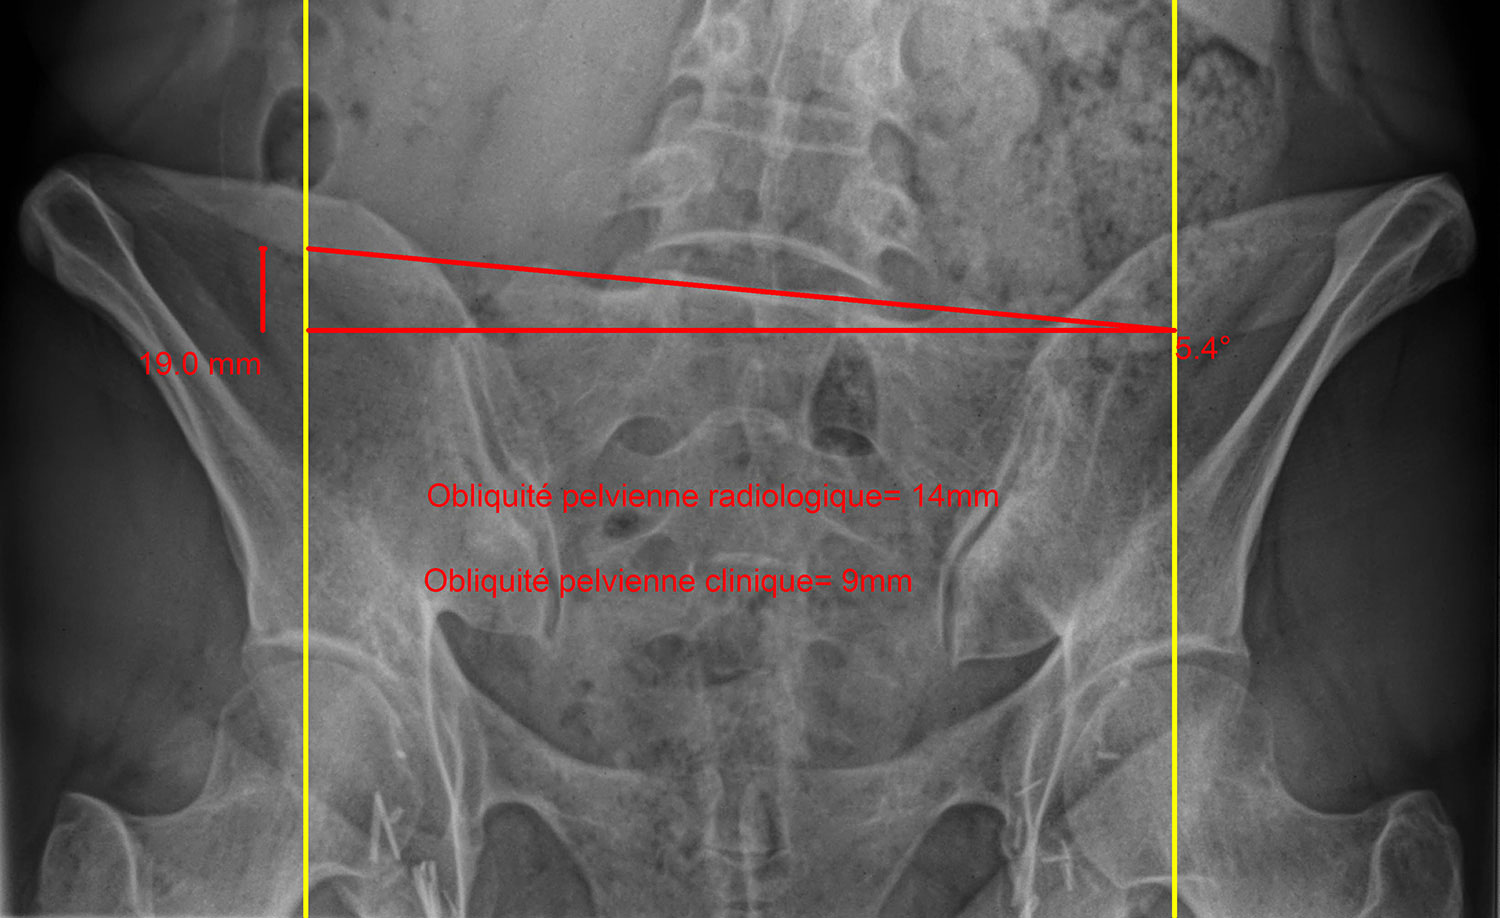

The method advocated by OrthoChiro chiropractors combines clinical (patient physical examination and muscular testing) and radiological assessments. First, we perform a visual appraisal of the patient’s overall posture including the pelvic area, then we observe their gait to identify any functional problems. Since an x-ray is only a 2D image of a 3D patient, it must always be interpreted with caution, which is why we save it for last and use it only to validate clinical observations.

Our method of radiological assessment of the pelvis is adapted from the Ferguson method, which according to our experience is much more clinically useful than a CT scan of the lower limbs. The 30° incline of the x-ray tube over a patient in frontal view allows for the simultaneous assessment of:

- hip height (femoral heads)

- pelvic bone (iliac) alignment

- disc inclination at the base of the sacrum—cornerstone that supports the spinal column and the entire weight of a person’s torso within their pelvis, transmitting it to the lower limbs. Because the sacroiliac joint barely moves at all (2° on each side), measurement in the coronal plane of disc L5-S1 inclination is therefore very representative of the mechanical constraints applied on the lower lumbar spinal column, provided, of course, that the x-ray be properly centred.

- lower lumbar spine alignment (L3-L4-L5) and potential compensations—it is crucial to take these into consideration so as not to undermine the patient should a shoe lift be considered.